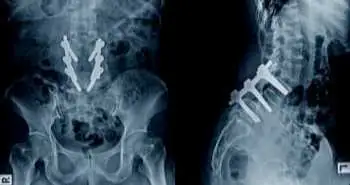

This randomized, double-blind, controlled clinical trial after lumbar interbody fusion was conducted to assess (a) Whether multimodal analgesia lower VAS (visual analog scale) pain scores by a clinically important amount

This randomized, double-blind, controlled clinical trial after lumbar interbody fusion was conducted to assess (a) Whether multimodal analgesia lower VAS (visual analog scale) pain scores by a clinically important amount (b) Does this analgesic approach minimize the amount of morphine patients consume after their surgery (c) Is this technique linked with fewer opioid-related side effects after surgery.

This study recruited 80 adult patients undergoing lumbar interbody fusion. The participants were randomly assigned into two groups: (1) Control group (n = 40) who received infiltration of the surgical incision at the end of the procedure with an injection of epinephrine 0.5 mg (0.5 mL) and 0.5% bupivacaine 100 mg (20 mL) (2) Multimodal group (n = 40), who received wound infiltration with the similar technique but with different medications: ketorolac 30 mg (1 mL), 0.5% bupivacaine 92.5 mg (18.5 mL), morphine 5 mg (0.5 mL), and epinephrine 0.5 mg (0.5 mL).